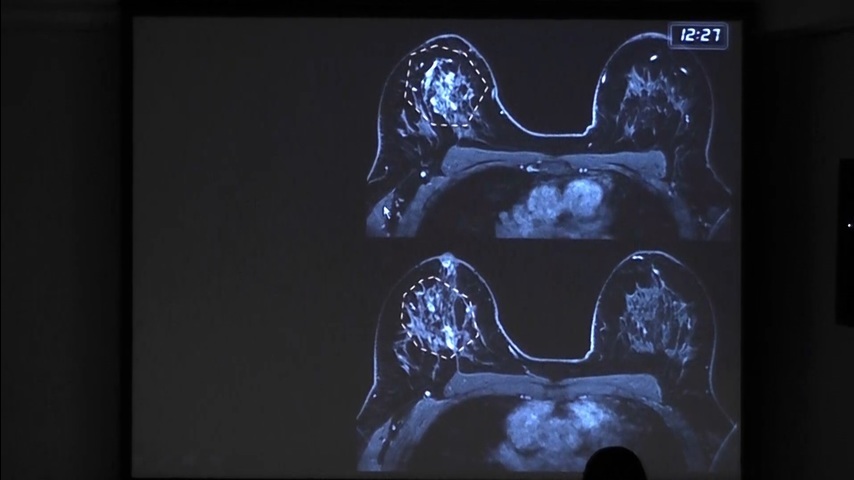

RESSONÂNCIA MAGNÉTICA DAS MAMAS: NOVO...

RESSONÂNCIA MAGNÉTICA DAS MAMAS: NOVOS PROTOCOLOS E ACR BIRADS™